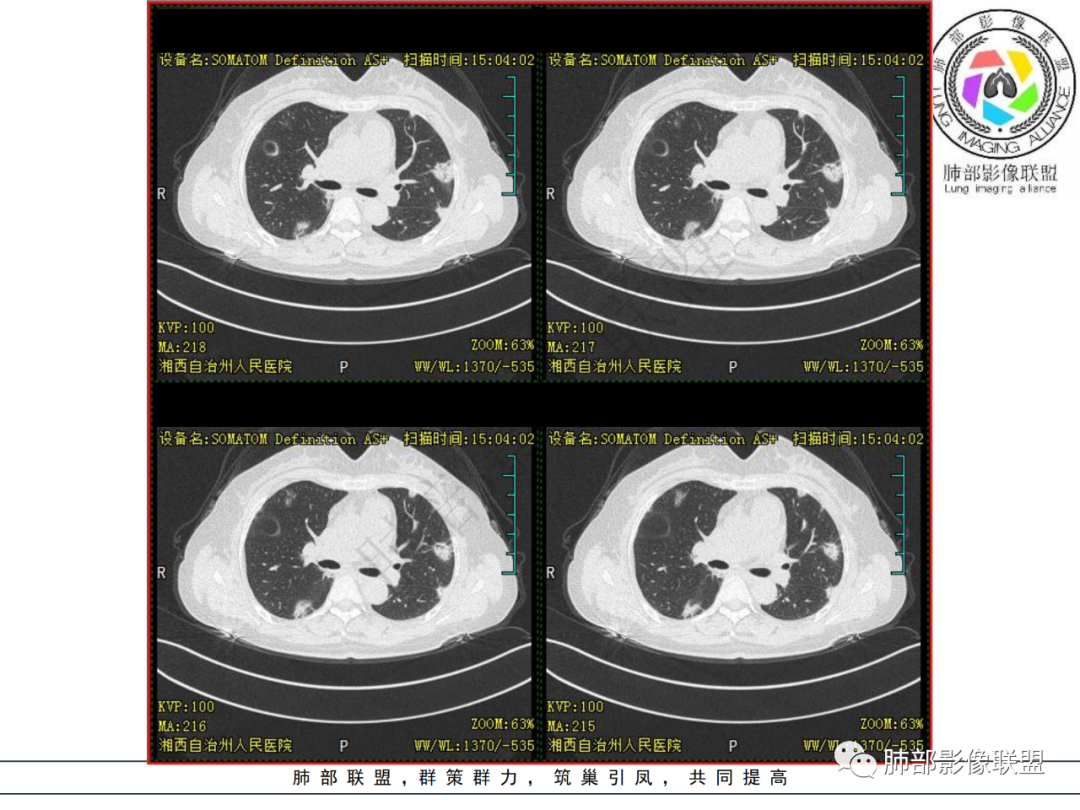

1.中年女性,发现双肺多发病变,且增多增大。

缺乏呼吸道症状及中毒症状,实验室炎性指标不高

既往多关节肿痛一年余,被诊断“类风湿”。此次就医无关节肿痛。

2.双肺多发片状影,胸膜下分布为主,部分沿支气管血管束分布,边界不清,实性及磨玻璃密度,趋于柔和,可见支气管进入或穿行,未见空洞、钙化及树芽等。部分病灶显示反晕。

3.未见腔积液。

4.双肺门及纵隔未见增大淋巴结。